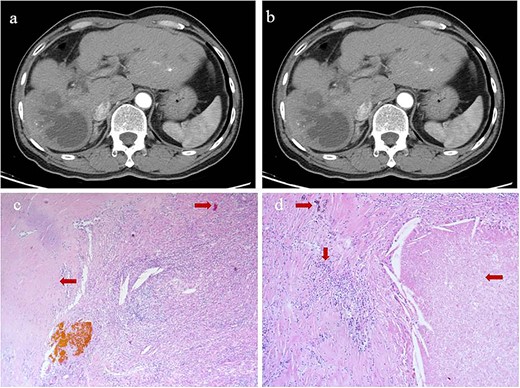

A 52-year-old Chinese man was admitted to our hospital after physical examination revealed hepatic occupation that had persisted for the previous month. The patient had been chronically infected with hepatitis B virus for more than 20 years, and he had been diagnosed with hypertension 12 months previously, which he kept under control with nifedipine. Physical examination revealed no other unusual findings. His Eastern Cooperative Oncology Group score was 0, Child-Pugh score was 5, indocyanine green retention was 4.8% at 15 min, and level of alpha fetoprotein in serum exceeded 2000 ng/ml, for which no dilution test was performed (Supplementary Table 1). Contrast-enhanced magnetic resonance imaging revealed two massive nodular tumors in the liver, one at the junction of the left inner and upper right anterior lobes, and the other in the lower right posterior lobe (Fig. 1a and b).

Contrast-enhanced magnetic resonance imaging at admission (upper row) and histopathology of primary tumors (lower row) of (a) the tumor at the junction of the left inner and upper right anterior lobes, and (b) the tumor in the lower right posterior lobe. Histopathology of the tumor in panels c and d showed tumor cells in Edmondson Grade II (leftward arrow), infiltration by macrophagocytes and lymphocytes (rightward arrow), and hepatocyte steatosis (downward arrows). Magnification, 40× in panel c or 100× in panel d.

The patient was diagnosed with HCC in Barcelona Clinic Liver Cancer Stage B. At 18 days after admission, the patient underwent hepatic resection of the right and middle lobes as well as cholecystectomy. Surgery proceeded uneventfully, and the patient recovered well. Postoperative histopathology confirmed that the two tumors were HCC and indicated an Edmondson grade of II (Fig. 1c and d). We detected one instance of microvascular invasion and one satellite nodule of Edmondson Grade II. Tumors expressed CK7 and glypican-3, but not CK19, based on immunohistochemistry. Surrounding liver tissue showed chronic changes associated with hepatitis, which we categorized as G1S1 on the inflammation grade (G) and fibrosis stage (S) [13].